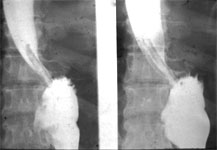

X-Ray showing In-Situ port for Chemotheraphy